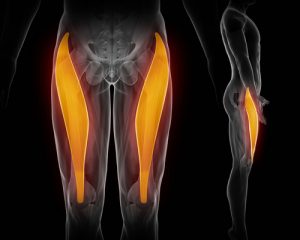

The pectineus muscle is in your adductor muscle group. The adductors are responsible for hip flexion and adduction.

Adduction is when you bring your leg closer to the opposite leg, such as when you cross your legs when you are sitting down. Athletes who play soccer, or who ride a horse, are heavily using their adductor muscles.

As you look at the graphic on the left, the muscles on the left side (right leg) are the larger adductor muscles.

As you look at the graphic on the left, the muscles on the left side (right leg) are the larger adductor muscles.